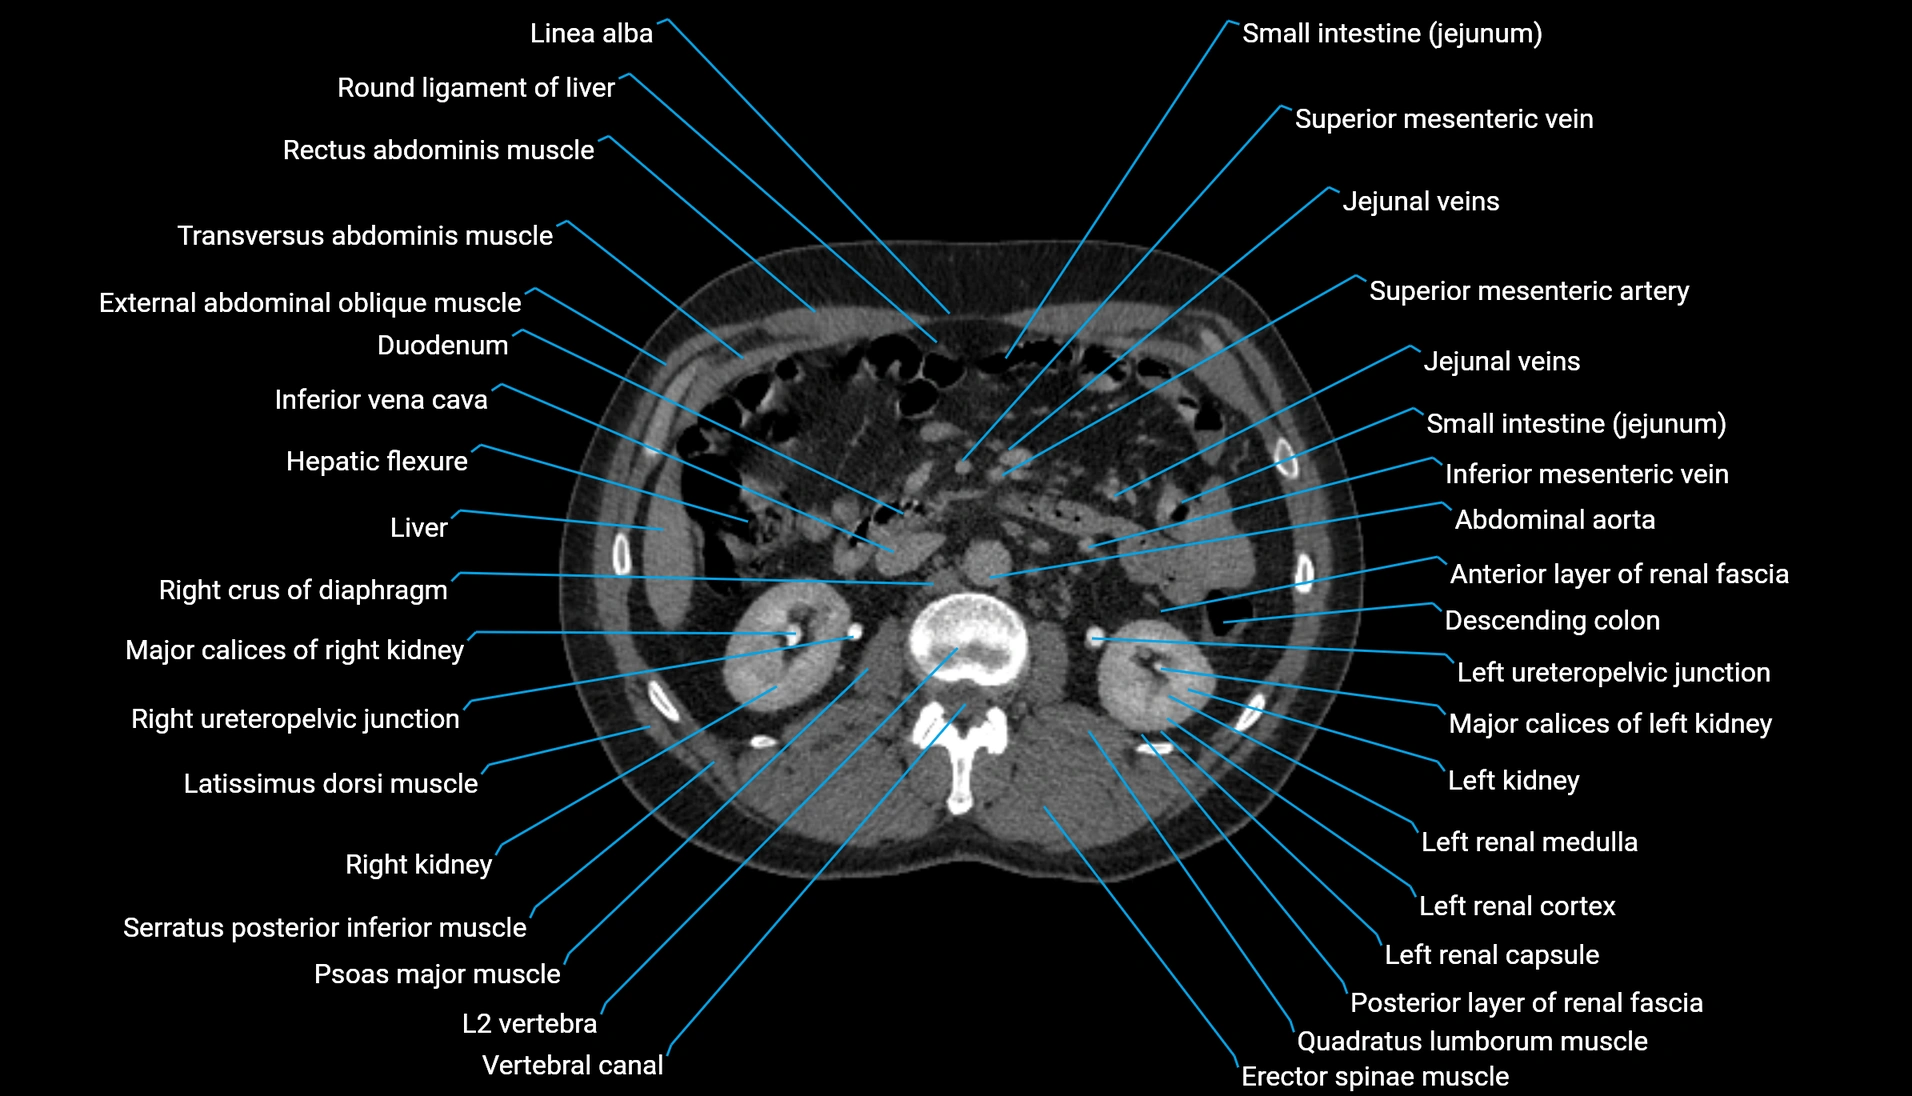

CT Appearance

Non-contrast CT:

-

Demonstrates cortical bone of acetabular rim in excellent detail

Detects fractures, dysplasia, retroversion, or bony overcoverage (pincer impingement)

3D reconstructions used in preoperative hip surgery planning

CT image